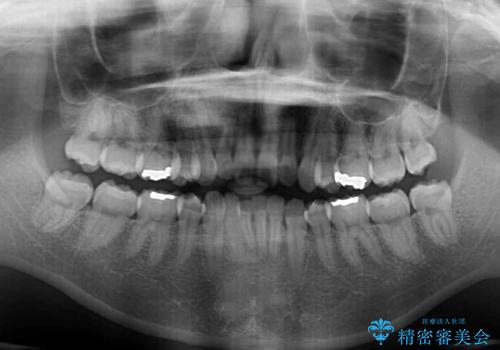

- 30代女性

- 下顎前歯を中心に、以前行った矯正治療の後戻りが気になるとのことで来院された患者様です。

後戻りは軽度であったため、インビザライン・ライトにて治療を行うこととしました。